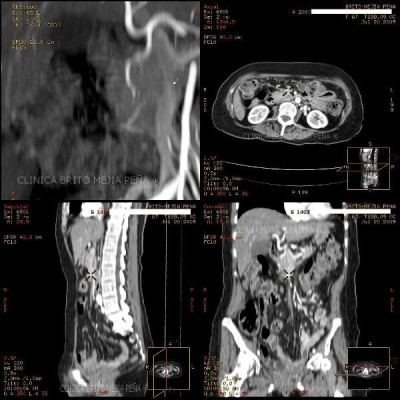

Metástasis hígado fase venosa